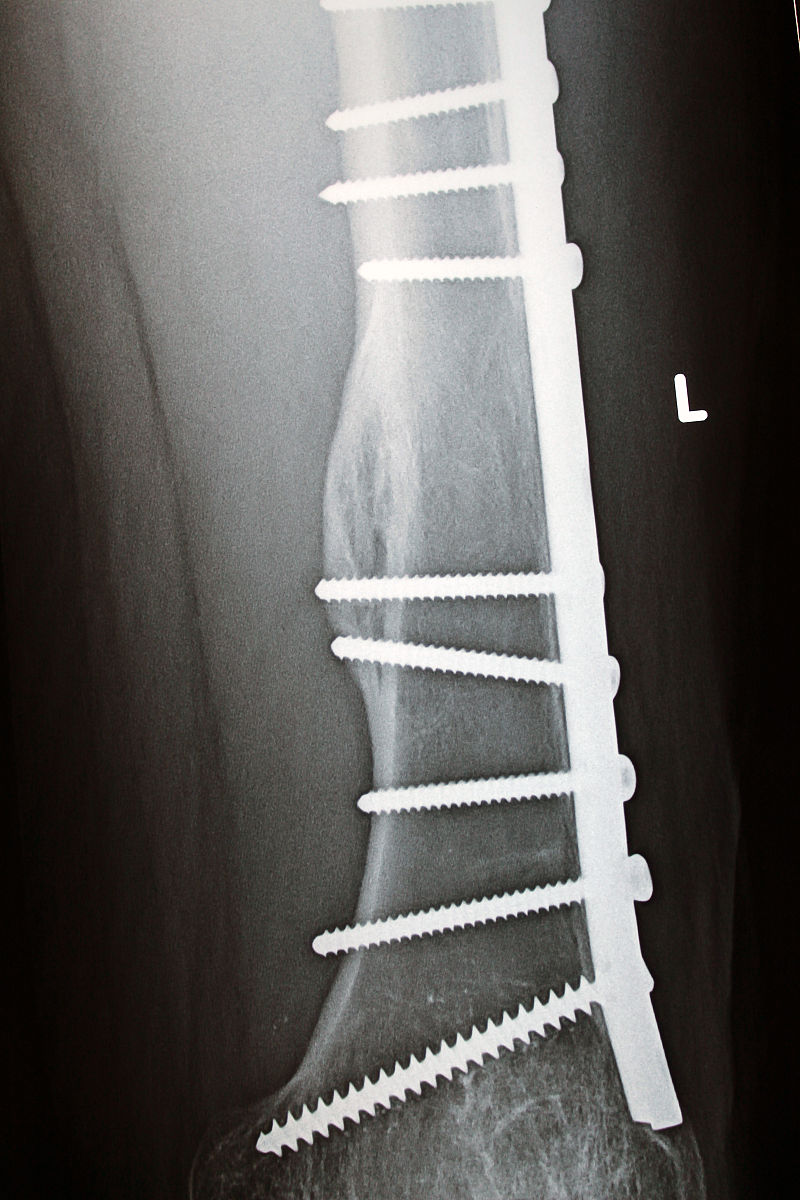

左股骨粗隆间骨折是一种常见的骨折类型,治疗方法多样。闭合复位PFNA内固定术是一种常用的治疗方法,其重要性主要体现在以下几个方面:

1. 促进骨折愈合:通过闭合复位PFNA内固定术,可以将骨折段复位并固定,稳定骨折端,促进骨折的愈合。内固定器材的使用可以提供足够的稳定性,减少骨折断端的移位,有利于骨折愈合。

3. 早期功能恢复:闭合复位PFNA内固定术可以提供稳定的内固定,使患者在早期就能够进行关节活动和负重,促进肌肉力量的恢复和关节功能的恢复。相比传统的外固定或开放手术,闭合复位PFNA内固定术的恢复时间更短,患者能够更早地恢复正常生活和工作。

综上所述,闭合复位PFNA内固定术对于左股骨粗隆间骨折的治疗具有重要的意义,可以促进骨折愈合,保护神经血管,促进早期功能恢复,减少并发症的发生。

左股骨粗隆间骨折患者闭合复位PFNA内固定术治疗的重要性